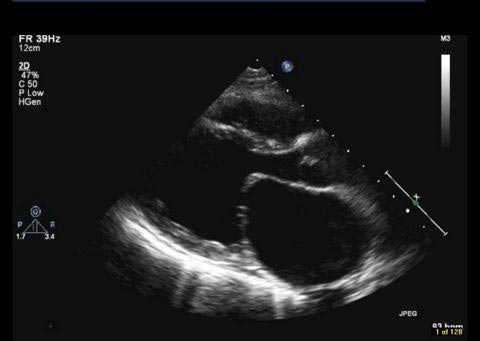

Στένωση Μιτροειδούς Βαλβίδας

Η μιτροειδής βαλβίδα φράσσει το αριστερό κολποκοιλιακό στόμιο. Η μιτροειδική συσκευή είναι μια πολύπλοκη δομή, αποτελούμενη από ινώδη δακτύλιο, δύο γλωχίνες, δύο θηλοειδείς μύες και τις τενόντιες χορδές. Το εμβαδόν του μιτροειδικού στομίου είναι 4-6cm2. H στένωση της μιτροειδούς είναι μια παθολογική οντότητα κατά την οποία μειώνεται το λειτουργικό στόμιο και παρεμποδίζεται η ροή αίματος από τον αριστερό κόλπο προς την αριστερή κοιλία. Η νόσος εγκαθίσταται βαθμιαία. Συχνότερο αίτιο είναι ο ρευματικός πυρετός, αλλά λόγω βελτίωσης των κοινωνικο/οικονομικών συνθηκών η επίπτωση της νόσου μειώθηκε σημαντικά. Δεν ισχύει βέβαια το ίδιο για τις αναπτυσσόμενες και υπανάπτυκτες χώρες. Λιγότερο συχνά αίτια στένωσης μιτροειδούς είναι η συγγενής στένωση, η ασβέστωση και τα δευτεροπαθή αίτια απόφραξης του χώρου εισόδου της αριστερής κοιλίας, όπως το σύνδρομο καρκινοειδούς, τα μυξώματα , οι εκβλαστήσεις και οι θρόμβοι. |